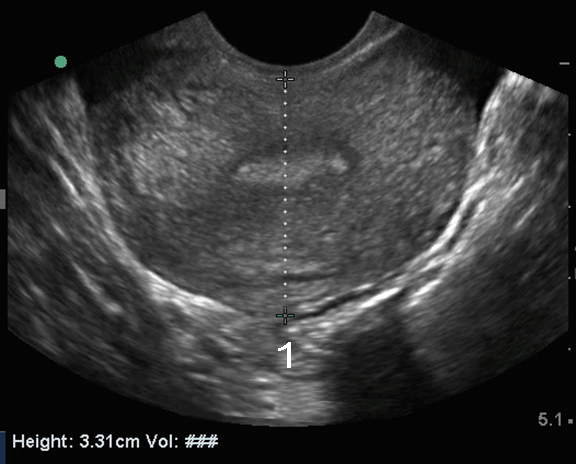

盆腔阴道内子宫横切面 2 图像